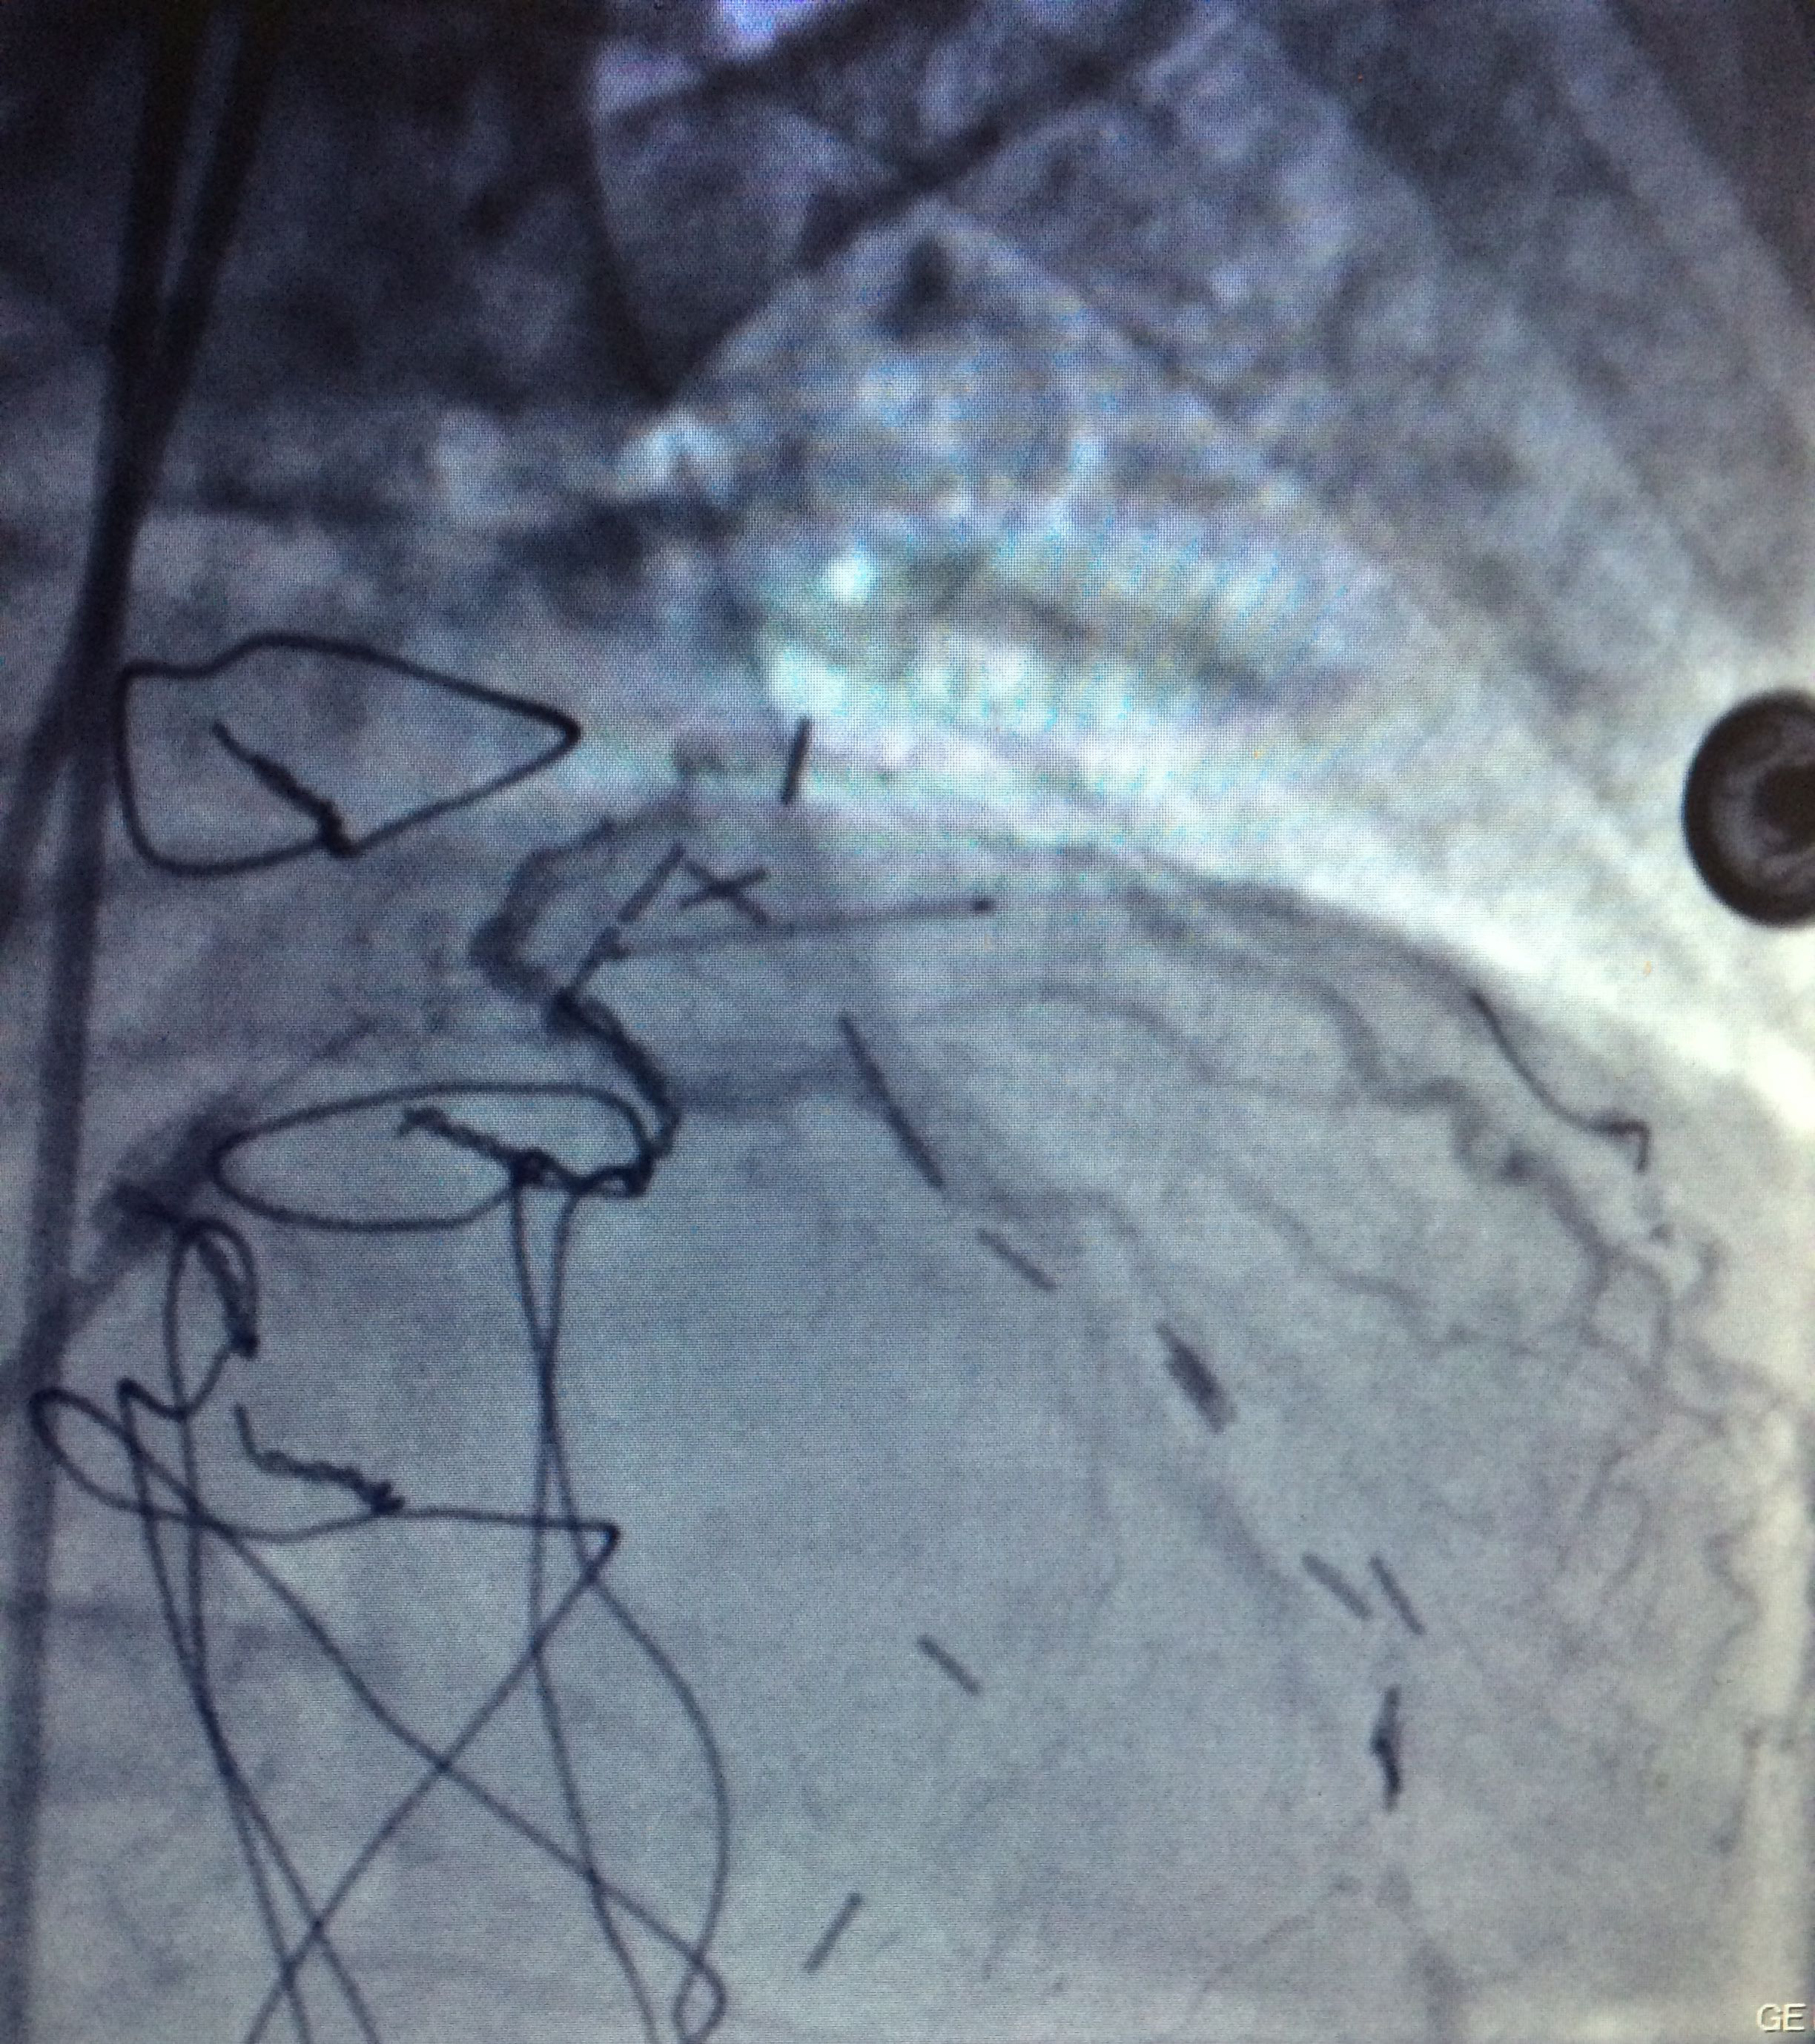

Figure 3 Through a conventional right femoral approach, the left coronary ostium was canalized using a 4.0 6Fr Launcher guiding catheter (Medtronic). Subsequently, a floppy microguide at the level of the anterior left descending artery was used to cross the lesion. Balloon dilation was performed to open the vessel starting with a 1.5x18mm Sprinter balloon (Medtronic) followed by a 2.0x22mm to finally deploy a 2.5x18mm Endeavor stent at 18atm for 10 seconds at the level of left anterior descending artery obtaining a satisfactory angiographic result.

Procedure

Through a conventional right femoral approach, the left coronary ostium was canalized using a 4.0 6Fr Launcher guiding catheter (Medtronic). Subsequently, a floppy micro guide at the level of the anterior left descending artery was used to cross the lesion. Balloon dilation was performed to open the vessel starting with a 1.5x18mm Sprinter balloon (Medtronic) followed by a 2.0x22mm to finally deploy a 2.5x18mm Endeavorstent at 18 atm for 10seconds at the level of left anterior descending artery obtaining a satisfactory angiographic result (Figure 3-6).

Figure 4 Through a conventional right femoral approach, the left coronary ostium was canalized using a 4.0 6Fr Launcher guiding catheter (Medtronic). Subsequently, a floppy microguide at the level of the anterior left descending artery was used to cross the lesion. Balloon dilation was performed to open the vessel starting with a 1.5x18mm Sprinter balloon (Medtronic) followed by a 2.0x22mm to finally deploy a 2.5x18mm Endeavor stent at 18atm for 10 seconds at the level of left anterior descending artery obtaining a satisfactory angiographic result.